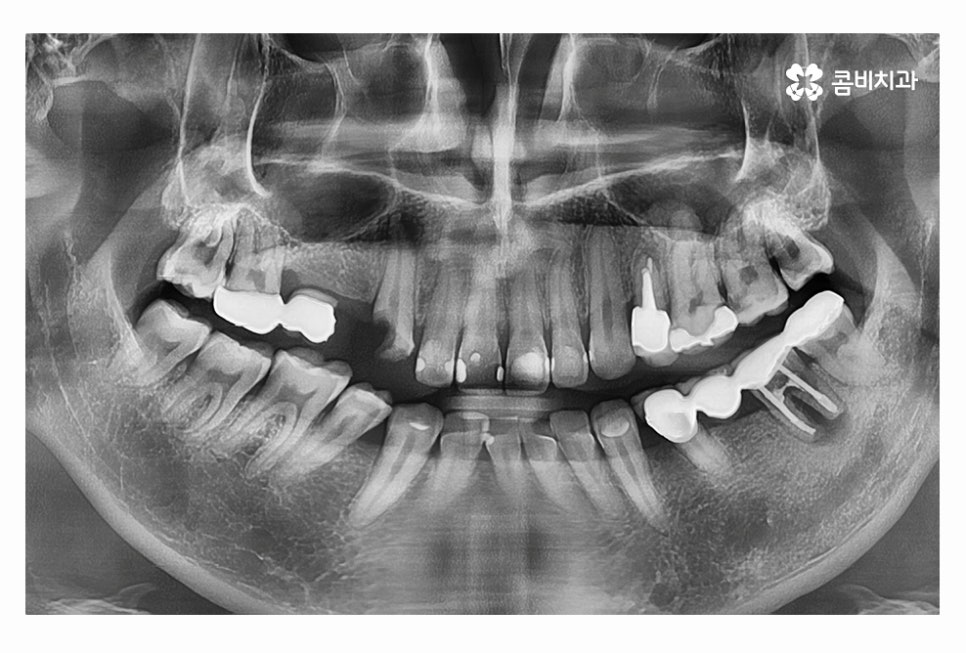

치아가 흔들리거나 빠지는 일은 노년층에게 있는 일이라고 생각하기 쉽지만 요즘 20대임플란트 환자분들이 나날이 늘고 있는데요. 20,30대에 치아를 잃는다면 대부분 사고로 인한 경우라고 생각되실 수 있겠지만 사고가 아닌 충치로 인한 경우도 크게 늘고 있어요. 젊은 환자분들의 경우 치아를 잃게 되었을 때 그 원...

치아가 흔들리거나 빠지는 일은 노년층에게 있는 일이라고

생각하기 쉽지만 요즘 20대임플란트 환자분들이 나날이 늘고 있는데요.

20,30대에 치아를 잃는다면 대부분 사고로 인한 경우라고

생각되실 수 있겠지만 사고가 아닌 충치로 인한 경우도 크게 늘고 있어요.

충치로 인해 치아를 잃게 되는 대표적인 사례라면

이미 과거에 치료를 했거나 치아 사이처럼 눈에 잘 띄지 않는 부위에

충치가 심해져서 치수 혹은 치아의 뿌리까지 손상이 심해진 경우라고 할 수 있어요.

충치는 누구나 발생할 수 있고 과거에 레진이나 인레이 등의 치료를

했던 분들이라면 시간이 지날수록 주변 치아 혹은 치료에 쓰인 재료가

손상, 마모 등을 거치게 되는데 치아 속에 2차 충치가 발생하는 경우에는

그로 인한 치아 손상이 심각한 상황으로 커지는 경우가 많다고 할 수 있어요.